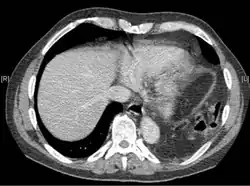

Physical examinations are not accurate, as there is usually no specific physical sign that can be used to diagnose this condition.[3] Thoracoscopic and laparoscopic methods can be accurate.[12] Chest X-ray is known to be unreliable in diagnosing diaphragmatic rupture;[4] it has low sensitivity and specificity for the injury.[5] Often another injury such as pulmonary contusion masks the injury on the X-ray film.[6] Half the time, initial X-rays are normal; in most of those that are not, hemothorax or pneumothorax is present.[4] A nasogastric tube from the stomach may appear on the film in the chest cavity; this sign is pathognomonic for diaphragmatic rupture, but it is rare.[4] The X-ray is better able to detect the injury when taken from the back with the person upright, but this is not usually possible because the person is usually not stable enough; thus it is usually taken from the front with the person lying supine.[5] Positive pressure ventilation helps keep the abdominal organs from herniating into the chest cavity, but this also can prevent the injury from being discovered on an X-ray.[4]

A CT scan has an increased accuracy of diagnosis over X-ray,[7] but no specific findings on a CT scan exist to establish a diagnosis.[9] The free edge of a ruptured diaphragm may curl and become perpendicular to the chest wall, a sign known as a dangling diaphragm. A herniated organ may constrict at the location of a rupture, a sign known as the collar sign. If the liver herniates through a rupture on the right side, it may produce two signs known as the hump and band signs. The hump sign is a form of the collar sign on the right. The band sign is a bright line that intersects the liver. it is believed to result due to the ruptured diaphragm compressing.[13] Although CT scanning increases chances that diaphragmatic rupture will be diagnosed before surgery, the rate of diagnosis before surgery is still only 31–43.5%.[7] Another diagnostic method is laparotomy, but this misses diaphragmatic ruptures up to 15% of the time.[4] Often diaphragmatic injury is discovered during a laparotomy that was undertaken because of another abdominal injury.[4] Because laparotomies are more common in those with penetrating trauma than compared to those who experienced a blunt force injury, diaphragmatic rupture is found more often in these people.[14] Thoracoscopy is more reliable in detecting diaphragmatic tears than laparotomy and is especially useful when chronic diaphragmatic hernia is suspected.[4]